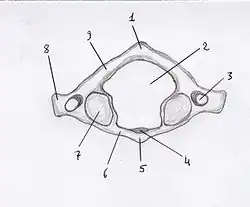

Il présente deux masses latérales unies par un arc osseux antérieur et un arc osseux postérieur. Ces quatre parties forment le foramen vertébral.

Les masses latérales présentent quatre faces : une supérieure, une inférieure, une latérale et une médiale.

Face supérieure

La face supérieure présente une surface articulaire concave : la cavité glénoïde allongée en avant et en dedans et souvent rétrécie dans sa partie médiane. Elle est orientée en haut et en dedans s'articulant avec le condyle occipital.

Face inférieure

La face inférieure présente une surface articulaire ovalaire plane orientée en bas et en dedans s'articule avec la facette articulaire supérieure de l'axis.

Face latérale

La face latérale se prolonge latéralement en avant et en arrière par les deux racines du processus transverse avec lequel ils délimitent le foramen transversaire (ou trou transversaire).

Face médiale

La face médiale présente dans sa partie antérieure un tubercule servant d'insertion au ligament transverse, tendu entre les deux tubercules droit et gauche..

Arc antérieur

L'arc antérieur est convexe en avant.

Sur sa face antérieure se trouve le tubercule antérieur de l'arc antérieur de l'atlas faisant point d'insertion du muscle long du cou et du ligament longitudinal antérieur.

Sur sa face postérieure se trouve une surface articulaire concave s'articulant avec le processus ondontoïde de l'axis formant la fossette odontoïde de l'atlas.

Arc postérieur

L'arc postérieur est convexe en arrière.

Sa face postérieure présente en son milieu le tubercule postérieur de l'atlas, point d'insertion des muscles petits droits postérieurs de la tête latéralement et du ligament nuchal médialement. Son bord supérieur est arrondi pour l'insertion de la membrane atlanto-occipitale postérieure. Son bord inférieur est une ligne d'insertion de la membrane atlanto-axoïdienne postérieure relié à l'axis en dessous

Sur sa face supérieure est visible un sillon (ou gouttière) de l'artère vertébrale pour le passage du premier nerf spinal et l'artère vertébrale et contribue au canal de l'artère vertébrale.

Foramen vertébral

Le foramen vertébral de l'atlas est le plus grand de l'ensemble des vertèbre. Le ligament transverse le divise en deux parties : une chambre antérieure et une chambre postérieure.

La chambre antérieure est quadrilatère et reçoit le processus odontoïde de l'axis. La chambre postérieure abrite la moelle allongée.